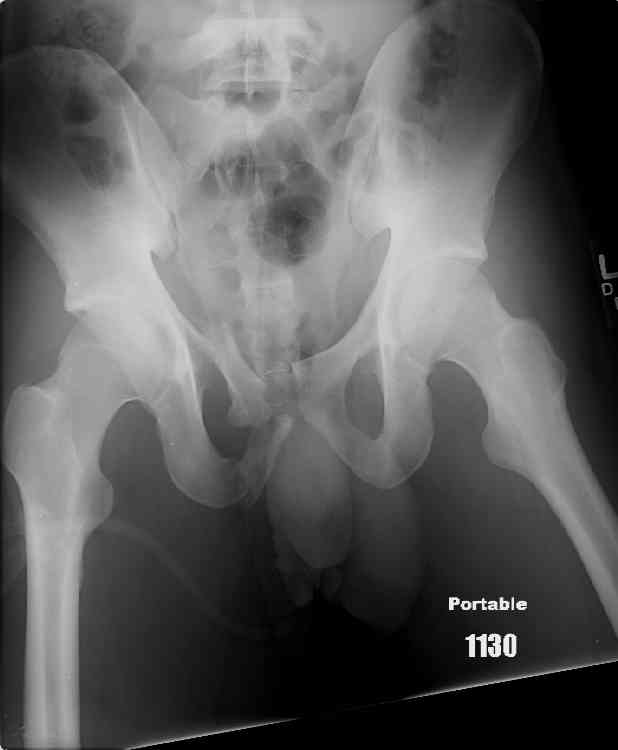

hello,this is a healthy 22yo male. peds vs auto.

no other injuries. has anyone treated these non-operatively? thanks.

It's type A pelvic-ring lesions. Because

the pelvic ring is stable, it

cannot be displaced by physiologic

forces and may be treated non-operativly in male.

One bit of important yet omitted info is the patient's physical exam... if this pelvic ring injury is unstable to exam, then I'd recommend operative reduction and stable fixation to him.